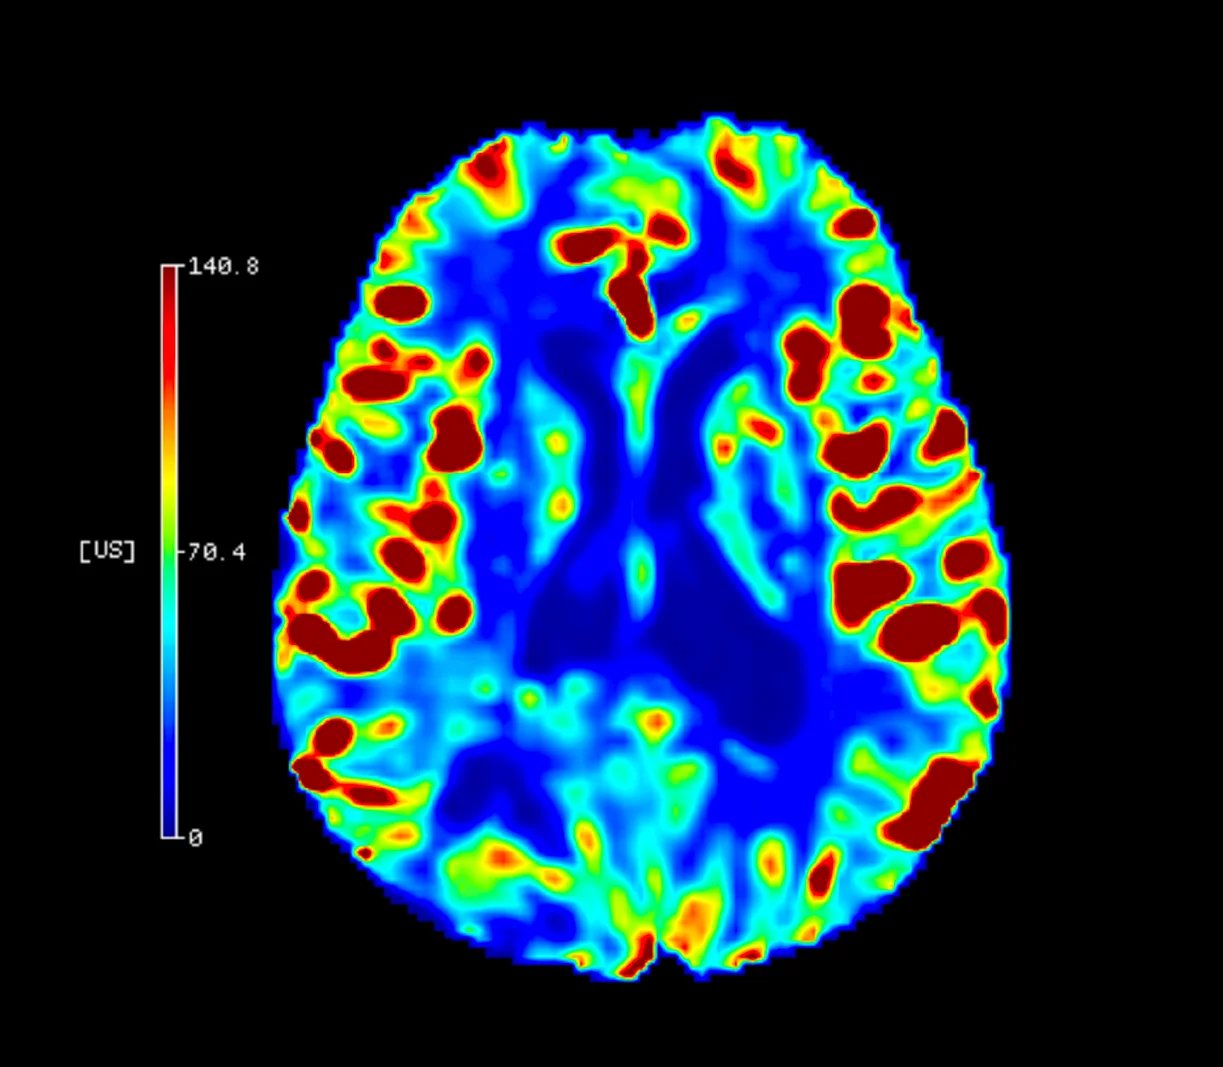

AI Tabanlı Lezyon Kantifikasyonu

Cercare Medical Neurosuite Stroke yazılımının Gelişmiş (Advanced) paketi, yapay zeka destekli algoritmalar ile lezyon kantifikasyonu sağlar. Derin öğrenme tabanlı modeller, binlerce hasta verisi üzerinden eğitilmiş olup, perfüzyon haritalarındaki doku değişimlerini otomatik olarak sınıflandırır. Böylece çekirdek infarkt (geri dönüşsüz doku) ve penumbra (kurtarılabilir doku) ayrımı, yalnızca eşik değer tabanlı hesaplamalara değil, çok boyutlu yapay zeka analizine dayanır.

AI tabanlı sistem, özellikle karmaşık vakalarda ve atipik perfüzyon paternlerinde, hekimlere daha güvenilir kantitatif veriler sunar. Klinik veriler, yapay zekâ destekli analizlerin tedaviye uygun hasta seçiminde doğruluğu %30’a kadar artırdığını ve gözden kaçan küçük lezyonların %20 daha fazla saptanabildiğini göstermektedir*.

Bu yaklaşım, yalnızca görüntüleme parametrelerini değil, aynı zamanda çoklu biyomarker kombinasyonlarını da analiz ederek tedavi kararlarının hızlanmasını sağlar.